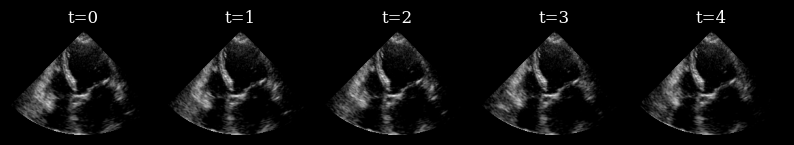

Visualize target sequence

Here we load a sequence of ultrasound frames from the CAMUS validation set. This will be our ‘ground truth’ target sequence, that the agent will need to reconstruct from a small budget of focused scan lines

[7]:

scan_convert = Pipeline([ScanConvert(order=2, jit_compile=False)])

parameters = {

"theta_range": [-0.78, 0.78],  # [-45, 45] in radians

"rho_range": [0, 1],

}

parameters = scan_convert.prepare_parameters(**parameters)

data_sc = scan_convert(data=data, **parameters)["data"]

n_frames_to_plot = 5

fig, _ = plot_image_grid(

data_sc[:n_frames_to_plot],

titles=[f"t={t}" for t in range(n_frames_to_plot)],

ncols=n_frames_to_plot,

remove_axis=True,

vmin=-1,

vmax=1,

)

zea: WARNING GPU support for order > 1 is not available. Disabling jit for ScanConvert.

../../_images/notebooks_agent_agent_example_12_1.png